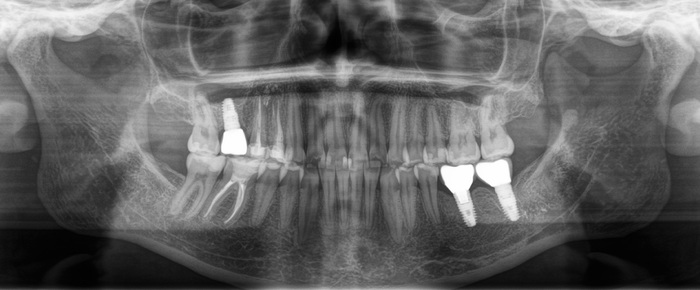

В январе 2018 молодой девушке была проведена имлантация в области 6го зуба на нижней челюсти слева, а коронка установлена в другом месте.

Ниже фрагмент компьютерной томографии, а интересующий имплантат справа снизу:

Для полной интеграции имплантата необходимо около 4х месяцев, но девушка пришла спустя 6, в июне 2018:

Жалоб нет, имплантат интегрирован. Следующим этом было снятие слепков и изготовление коронки. Ниже снимок от августа 2018:

Казалось, что все в порядке. Так, собственно, оно и было. Контрольный снимок в декабре 2019: